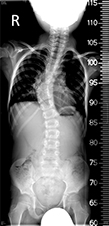

Súlyos esetek műtéti kezelése

Csigolyafejlődési rendelenesség - röntgenA csigolyafejlődési rendellenesség nagy progresszióra (romlásra) hajlamos elváltozás, súlyos gerincdeformitás, gerincferdülés kialakulásához vezethet. Korai diagnózisa, kompetens gerincsebész által történő rendszeres megfigyelése, vizsgálata ezért rendkívül fontos. A súlyos gerincdeformitás, gerincferdülés kezelése a csontos érettség beállta után (pubertáskorban, felnőttkorban) ún. gerinckorrekciós műtéttel történik. Ez egy nagyobb megterheléssel járó beavatkozás, amely hosszabb műtéti időt, több implantátum alkalmazását, jelentősebb műtéti kockázatot jelent, de a beavatkozást követően lényegében teljes élet élhető (a korrigált és implantátumokkal rögzített gerincszakaszhoz, vagy teljes gerinchez adaptált mozgás, sport, életmód).